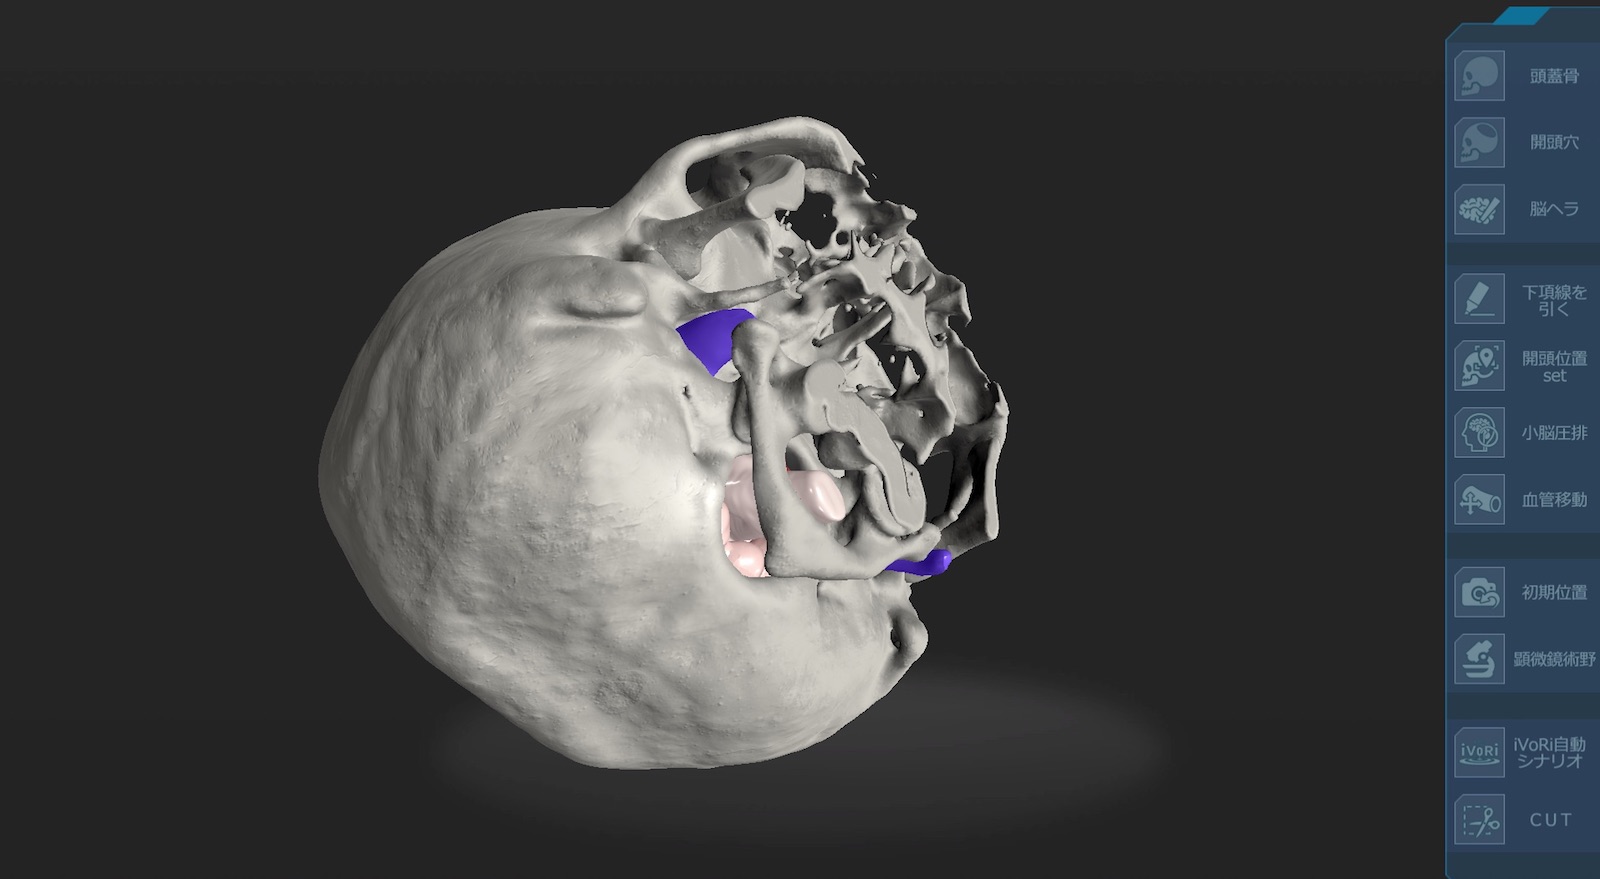

脳神経画像解剖ナビゲーション: 正常・変異・異常との比較で読影。脳の機能解剖とリハビリテーション | 金子 唯史 |本 | 通販 | Amazon。脳神経画像解剖ナビゲーション: 正常・変異・異常との比較で読影。金芽ロウカット玄米 2kg x4袋 東洋ライス。「脳神経画像解剖ナビゲーション = NAVIGATION OF IMAGING ANATOMY:CENTRAL NERVOUS SYSTEM : 正常・変異・異常との比較で読影に役立つ!」岡本 浩一郎 / 岡本 浩一郎定価: ¥ 9400#岡本浩一郎 #岡本_浩一郎 #岡本浩一郎 #岡本_浩一郎 #本 #自然/医療・薬学・健康○ 裁断について業者による裁断後の商品です。脳神経画像解剖ナビゲーション 正常・変異・異常との比較で読影。裁断済みのため、商品の状態は\"全体的に悪い\"にしています。ケーススタディで学ぶ 脳動脈瘤クリッピングの5ステップ - 株式。裁断について御理解のある方のみでお願い致します。メジカルビュー社|脳神経外科|エッセンシャル頭蓋底外科[Web。○ その他状態についてマーカーや書き込みはなしですが、素人検品である旨をご承知おき下さい。脳卒中後の病的な痛みに関連する大脳皮質の縮小信号を検出。スキャナ読み込みの段階でページの入れ替わりが稀にありますが、抜けはございません。01 脳のvascular territoryと脳葉の画像解剖 | 画像診断情報。ご確認ください。リハに活かす!機能解剖から学ぶ脳画像の読み方〜症状・経過。○ その他注意点返品・交換は承っておりません。NEXT FIELD 5:異分野間の連携が革命を起こす〜Mayaを操る脳神経。ご了承ください。Untitled Page。素人管理であることをご理解の上、ご購入ください。脳手術 AIシミュレーター『Hana』 – ポケクエ。他の商品と同時購入でしたら割引いたします。産科と婦人科増刊号 ホルモン療法 裁断すみ。その他なにかご要望ありましたら、気軽にコメントください。世界の見方の転換1、2、3。